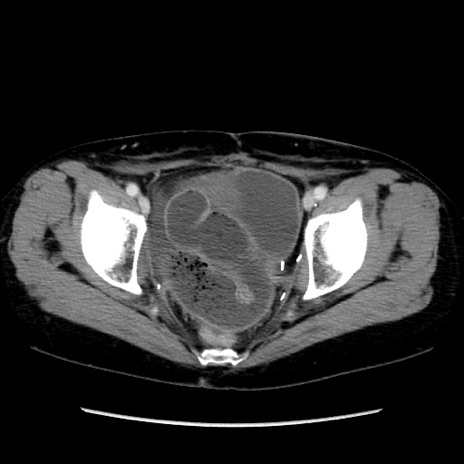

症例32(横断像)

【症例】40歳代 女性

【主訴】上腹部痛、嘔気・嘔吐

【現病歴】約9時間前頃から急に上腹部痛、嘔気、嘔吐が出現。改善しないため救急要請。

【既往歴】子宮頚癌(広汎子宮全摘術、放射線療法)、腸閉塞

【身体所見】腹部:平坦、軟、腸雑音亢進、上腹部を中心に腹部全体に圧痛あり。

【データ】WBC 8400、CRP 0.03